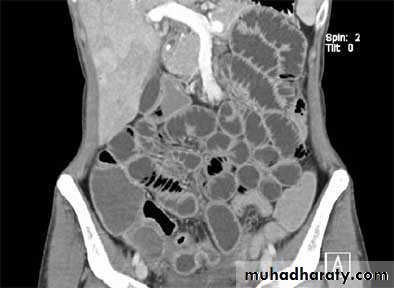

Diverticular disease

• Out-pouching of the mucosa through the muscular layer of the bowel wall

• Very common particularly in adults, commonest in the sigmoid.

• The diverticulae when filled with barium produce a spherical out-pouching with an narrowed neck (diverticulosis), some pouches do not fill with barium when inflamed (diverticulitis) causing symptoms such as sepsis, diarrhea or obstruction.

• The colon may show "saw tooth serrated" appearance from muscle hypertrophy.

• More extensive lesions produce perforation with fistulae into the bladder, small intestine or vagina, pericolic abscess and sometimes pneumoperitoneum.

• A stricture may occur in an area of recognizable diverticular disease otherwise cannot be differentiated from carcinoma.